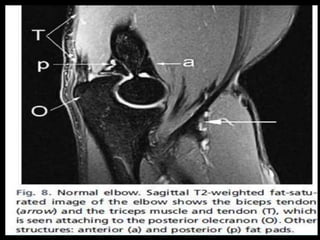

Elbow Joint.